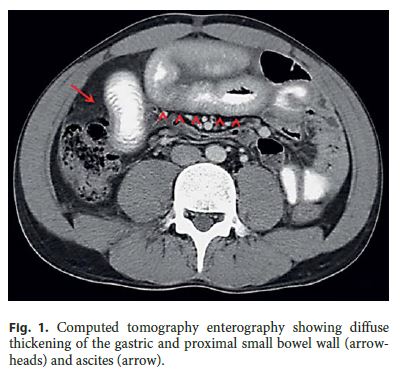

Abdominal ultrasound confirmed moderate ascites, and computed tomography enterography (fig. 1) showed diffuse thickening of the gastric and proximal small bowel wall (arrowheads) and peritoneal fluid (arrow). Ascitic fluid analysis after an abdominal tap revealed a serum-ascites albumin gradient <1.1 g/dL and significant eosinophilia (fig. 2, inset).